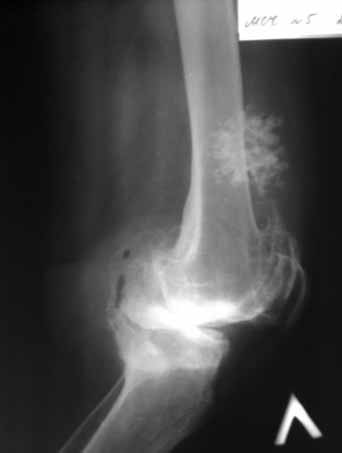

Пациентка 72 лет.Не обследовалась и не лечилась.

Работала поварихой до последнего времени.обратилась за медпомощью впервые.ходит без дополнительной опоры. Основные жалобы на ограничение движений и боли в правом коленном суставе.

Финансовые возможности ограничены.Чем можно помочь? Артродез? Протезирование?

Здравствуйте! А у вас нет ли R-гр? Для установления ст. артроза. Если же пациентка обращается первично, может стоит попробовать консервативное лечение?! НПВП, физиолечение, массаж, внутрисуставные блокады... Артродез и протезирование думаю всегда успеется.

однозначно протезирование

Anatoly Yakushin 08 Апрель 2011, 05:58

Больной несомненно показано эндопротезирование, однако случай не простой. Если у Вас нет достаточного опыта в проведении подобных операций, лучше направить больную в соответствующее лечебное

учреждение. По квоте.